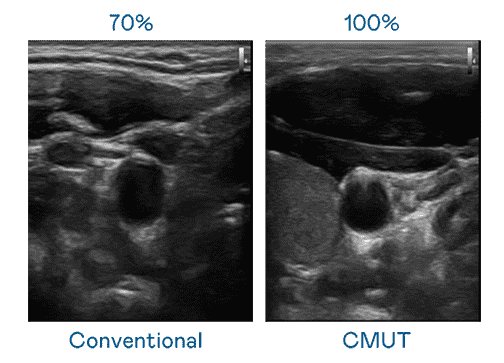

CMUT 技术是一种用电容式微机电元件来产生超音波讯号的技术。。。。与传统 PZT 压电式技术相比,,,CMUT 频宽增加 30%,,,更宽频的超音波讯号让影像解析度大幅提升,,,,是实现高影像品质医疗超音波扫描、、促进精准医疗发展的关键技术。。。

超音波影像的解析度高低,,,,首先取决于探头能发出的讯号频宽。。。。人生就是博 CMUT 可提供高清晰的超音波讯号,,提供高频宽、、、高灵敏度、、、、影像纹理细节更高的超音波影像,,协助医护人员缩短影像判读时间及利用精准的医疗影像进行诊断。。